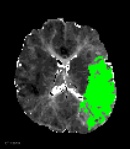

南京市第一医院是国家卫生健康委首批高级卒中中心,设有独立的神经内科急诊及脑血管病绿色诊疗通道。接诊的侯建康主治医师第一时间启动绿通,完善了头部磁共振及血管成像检查,明确了王先生急性缺血性脑梗死的诊断,而梗死原因是王先生脑内两根非常重要的血管(左侧颈动脉和左侧大脑中动脉)发生了堵塞。

手术过程中,侯建康主治医师发现了王先生血管堵塞的前因后果:左侧颈动脉形成了动脉夹层,夹层进一步诱发血栓形成;而形成的血栓被血流冲刷脱落,进一步堵塞了远端的大脑中动脉。在施洪超主任医师指导下,侯建康主治医师使用抽吸导管将脱落到大脑中动脉的血栓抽吸了出来,随后在动脉夹层的部位植入了一枚支架以重建管腔。

两根堵塞的血管均被重新开通,脑组织迅速得到了血液供应,王先生得救了!